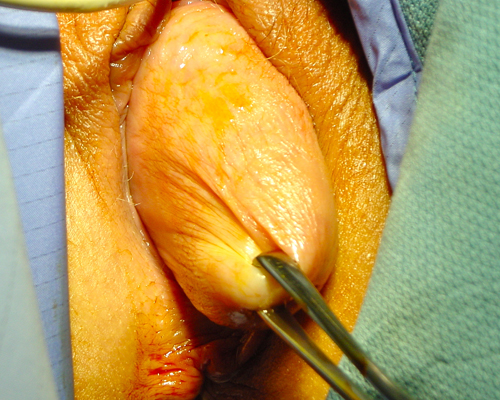

After this patient was put to sleep the prolapse is assessed and the uterus is shown to come outside the introitus.

She underwent a laparoscopic hysterectomy and complete pelvic floor reconstruction including the perineum (area between the vagina and the anus). The final result is shown.